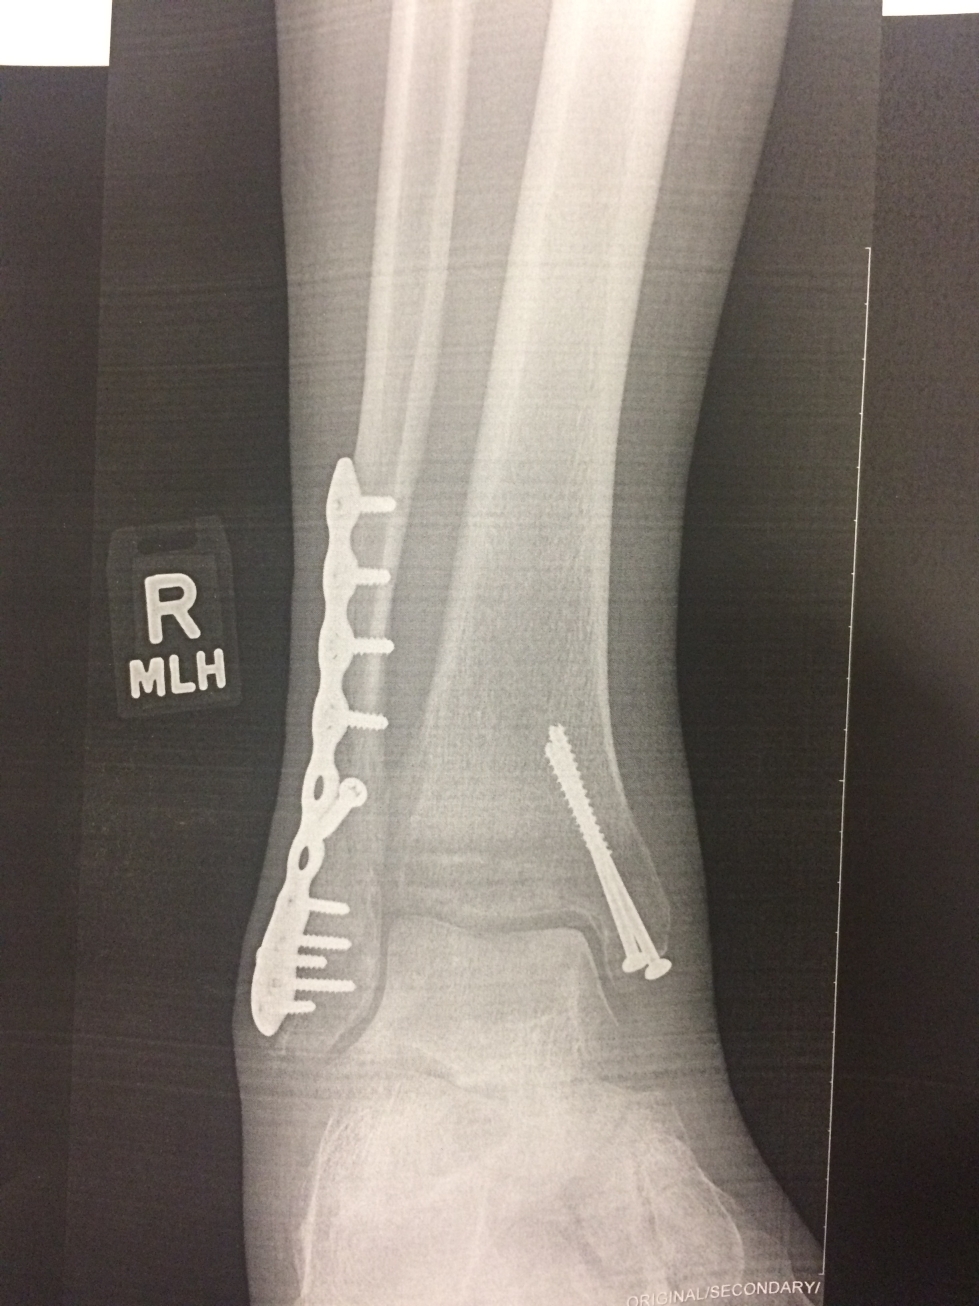

I got home about 2PM on Friday afternoon August 9th. Not a good time to get in to see a doctor. Kay took one look at my ankle and called to schedule an immediate appointment with an orthepedic surgeon. I was getting X-Rays just after 3PM. The tech handed me a printout. Even an amateur could see a clean break in the fibula. Kay also pointed out a problem with the end of the tibia (medial malleolus).

The bones healed quickly: six weeks in a cast/splint. But, I was shocked when the cast finally came off at how much the muscles and tendons had deteriorated. Seven months of continuous exercise brought be up to hiking level as measured by hiking and jogging times around my standard courses.